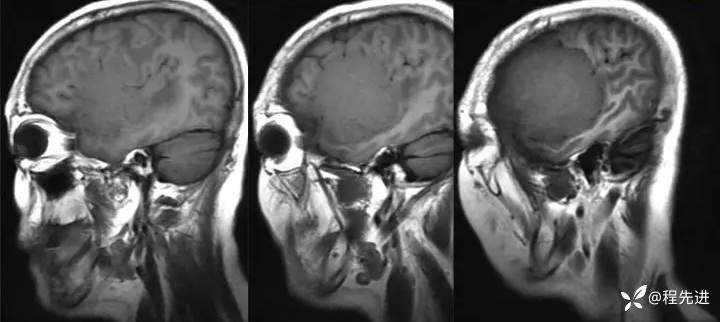

【患者信息】:女,58岁

【现病史及既往史】:发现头皮肿块,进行性增大2年余

【检查】

影像检查: